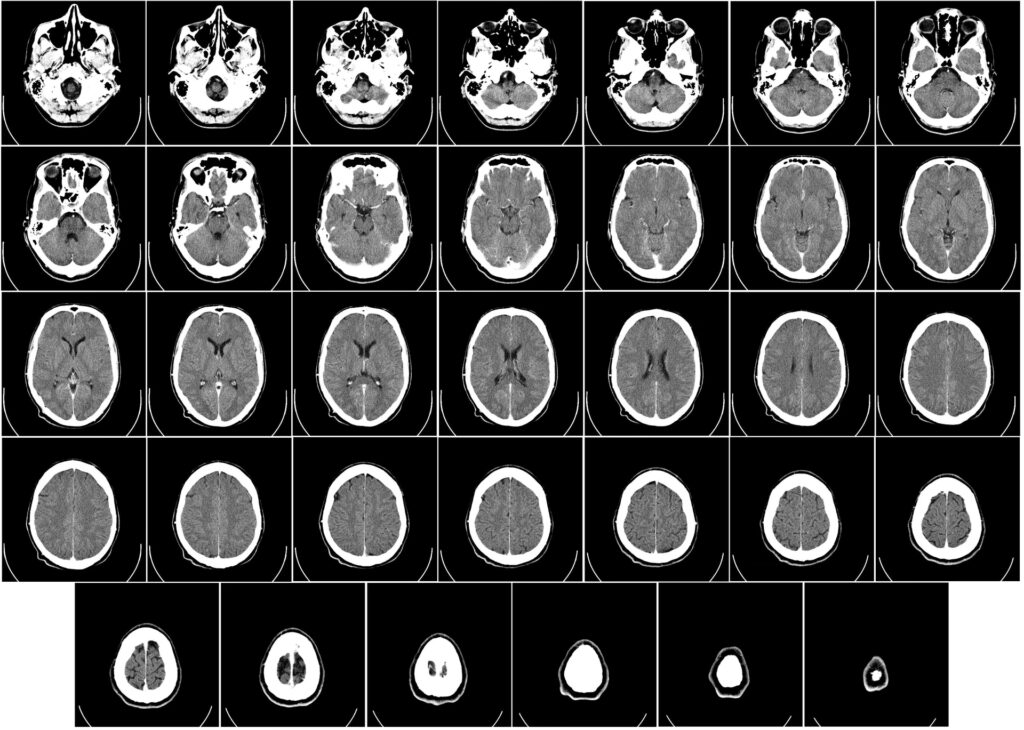

La TC, o Tomografía Computarizada, es una técnica de imagen médica que utiliza rayos X y procesamiento informático avanzado para crear imágenes transversales detalladas del cuerpo. A diferencia de una radiografía convencional que produce una imagen bidimensional de estructuras superpuestas, la TC genera "cortes" o "rebanadas" virtuales del área examinada. Piensa en ello como si pudieras cortar una hogaza de pan y examinar cada rebanada individualmente; la TC hace algo similar con el cuerpo, permitiendo a los médicos ver estructuras internas sin superposición.

En neurología, la TC se enfoca específicamente en la cabeza y el cerebro. Proporciona imágenes detalladas del tejido cerebral, los huesos del cráneo, los vasos sanguíneos principales y otras estructuras intracraneales. Su capacidad para distinguir entre diferentes densidades de tejido (como hueso, aire, líquido cefalorraquídeo, tejido cerebral normal y sangre) la hace invaluable para detectar anomalías.

Estas "rebanadas" se visualizan típicamente en tonos de gris, donde el hueso aparece blanco (alta densidad), el aire y el líquido cefalorraquídeo aparecen oscuros (baja densidad), y el tejido cerebral aparece en varios tonos de gris intermedios. La capacidad de la computadora para procesar rápidamente los datos y generar imágenes es lo que hace que la TC sea tan rápida y útil en situaciones de emergencia.